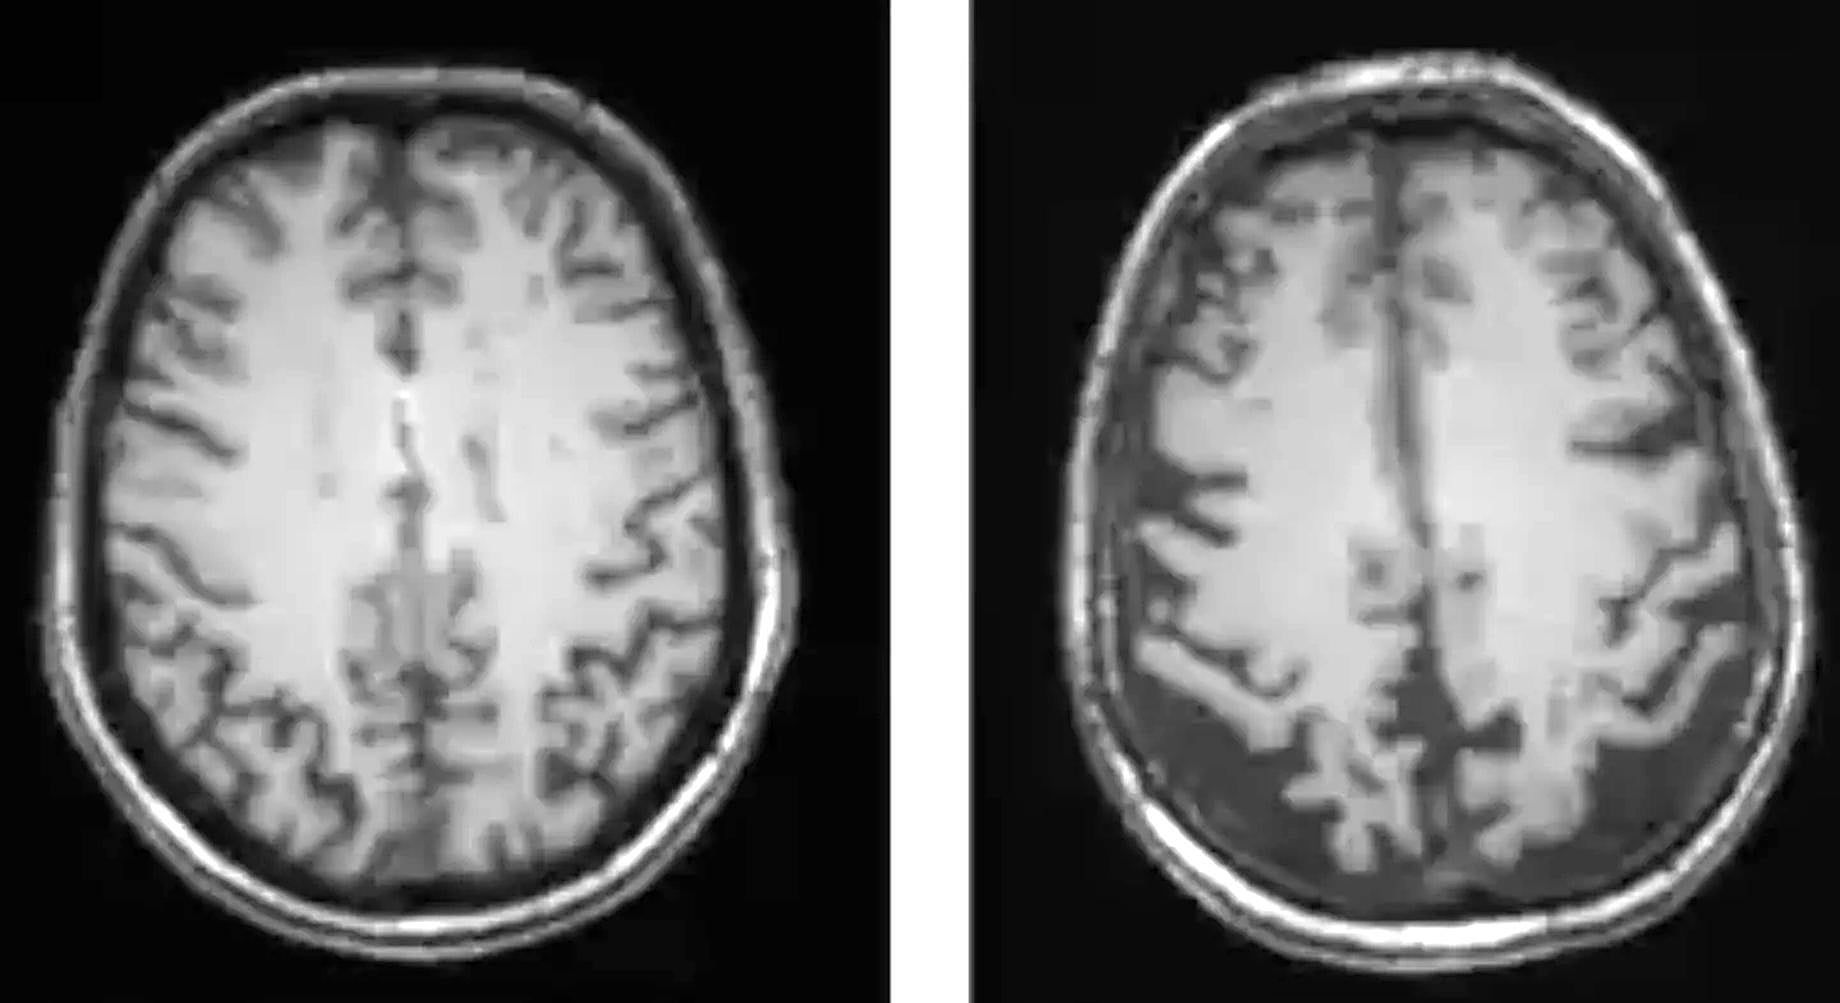

Solo se puede diagnosticar con un 100% de seguridad en la autopsia

Es una de las «'neuroleyendas' urbanas» más extendidas sobre la enfermedad de Alzheimer, a juicio de Martínez-Lage. «Mentira podrida. Se puede diagnosticar con un altísimo grado de fiabilidad hoy en día en vida de la persona gracias a los biomarcadores», sostiene. La evaluación es clínica y se basa en tres datos que el médico investiga con los medios adecuados. Por un lado, la presencia de los síntomas y los signos típicos de la enfermedad y su confirmación con pruebas de memoria y otras funciones cognitivas. Por otro lado, la presencia de cambios en el cerebro por pruebas de imagen cerebral.

Finalmente, la historia clínica, la exploración neurológica, las pruebas de imagen cerebral y los análisis de sangre permiten sospechar y descartar otras posibles causas que van desde los procesos vasculares o los tumores cerebrales, hasta la hidrocefalia, enfermedades del hígado o el riñón, enfermedades endocrinológicas como el hipotiroidismo, déficit de vitaminas o ácido fólico o incluso otras enfermedades neurodegenerativas como el párkinson, la enfermedad con cuerpos de Lewy o las degeneraciones frontotemporales.